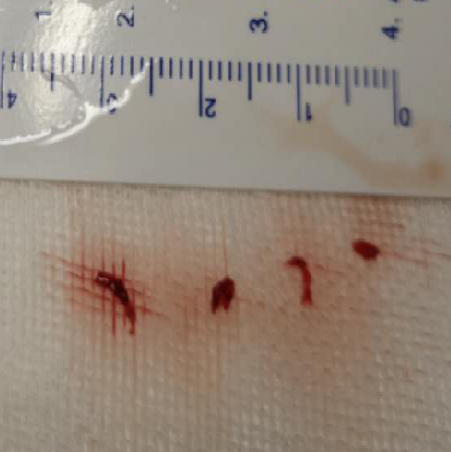

2、SWIM操作:0.014”微导丝+Rebar 18微导管通过LMCA M1段,手推造影剂示真腔,撤出微导丝,通过微导管将Solitaire 6-30支架输送至M1段,缓慢释放支架,远端在M1中段,近端在床突段,造影可见左侧前向血流部分恢复,眼动脉显影良好,眼动脉段可见充盈缺损。等待5分钟,推送React™ 68导管至支架近段,负压抽吸并缓慢回撤支架,然后撤出导管。可见支架体附着质软红色血栓,导管内抽出大量细碎的栓子。

本例患者,既往无明显内科疾病,常年吸烟史,通过造影可见,左侧颈内动脉眼动脉段重度狭窄,和前交通代偿血流形成对抗血流,当血栓形成并进一步加重时,狭窄处的前向血流减弱,进而狭窄的近端和远端不断形成血栓。患者症状在静脉溶栓时出现症状的减轻后再加重的波动,可能也与远端栓子脱落有关,尽早开通病灶侧的血管仍是必要的。取出的栓子质地较软、新鲜,考虑以红血栓为主,也印证这点。